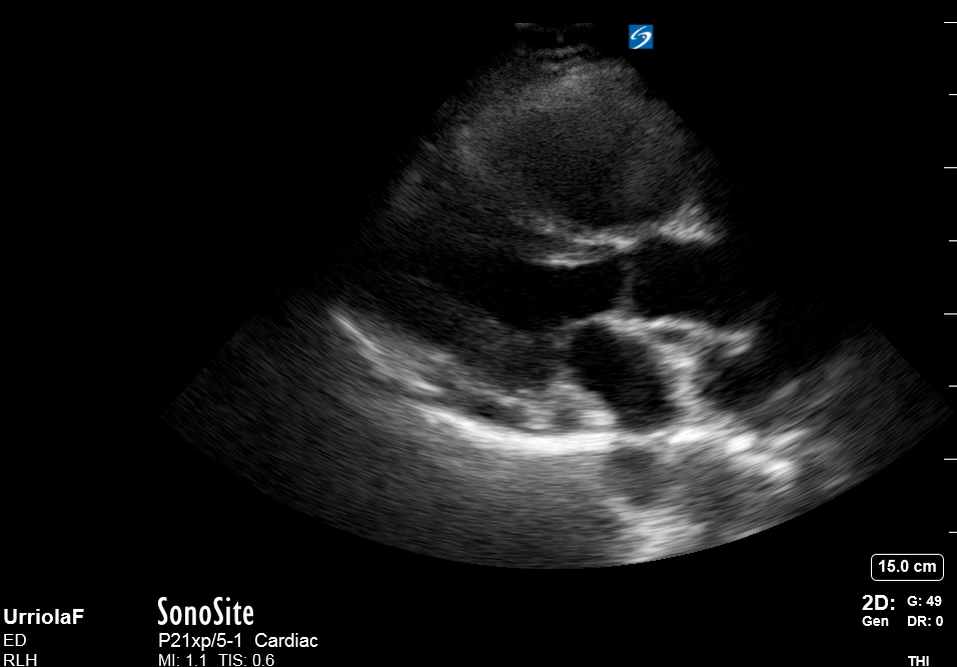

THE VIEWS

The A4C view provides an accurate chamber size comparison. However, achieving a proper A4C view (avoiding foreshortening or ballooning, and visualising the four chambers with a vertically oriented interventricular septum) can be a challenging exercise of image acquisition. Additionally, the PSAX view at the level of the papillary muscles shows both LV and RV side by side and is useful to assess function and size. When RV pressure is high, the septum will be pushed and flattened towards the LV, resulting in the characteristic “D-shaped” LV or “D sign”.

When the pulmonary artery pressure rises, the RV will dilate, altering the normal RV:LV ratio. Although sacrificing sensitivity, the use of equality (1:1 ratio) as a cutoff can achieve a specific estimation of RV strain. If imaged correctly by a trained operator, the presence of an RV:LV ratio > 1 is highly specific for RV strain.

RV dilation can be acute, chronic, or acute-on-chronic. However, in patients presenting with undifferentiated chest pain, shortness of breath, hypotension or syncope, the presence of any RV dilation should raise suspicion for acute pulmonary embolism (PE). Furthermore, in a patient in shock, the presence of RV strain may signal the need for aggressive therapy – emergency thrombolysis.